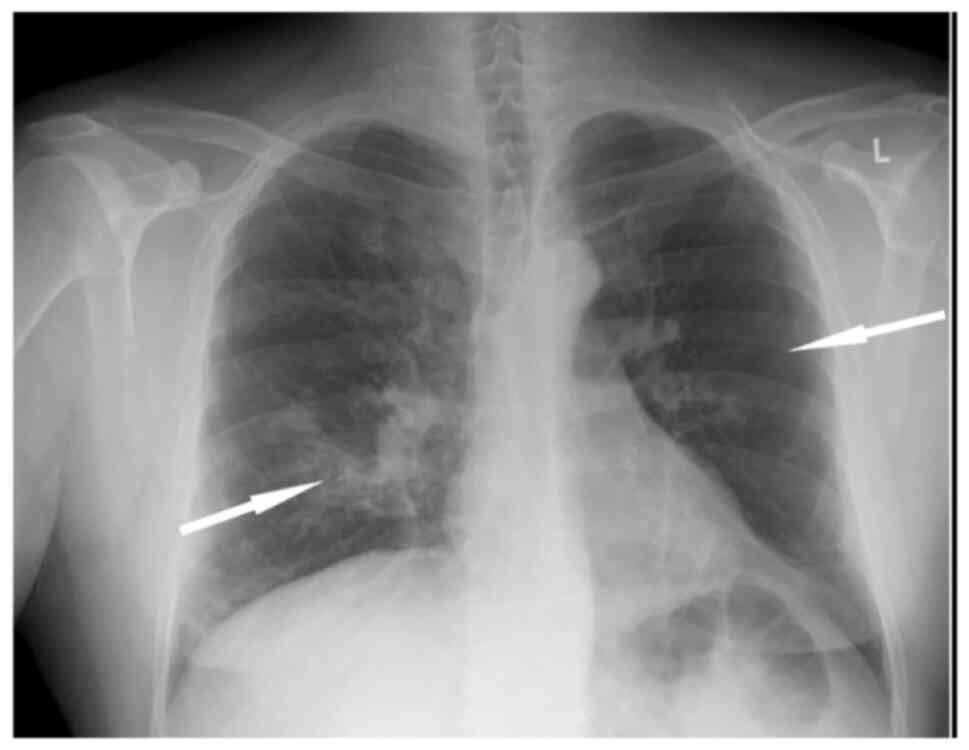

Arterial blood gas analysis revealed a partial pressure of oxygen (pO2) of 56 mmHg, a partial pressure of carbon dioxide (pCO2) of 28 mmHg, pH 7.51 and bicarbonate (HCO3-) levels of 22.3 mmol/l in room air. A chest X-ray revealed patchy infiltrates in the right lung lower lobe and a hyperlucent left lung (Fig. 1).

Figure 1

Chest X-ray illustrating patchy infiltrates in the right lung lower lobe (arrow) and a hyperlucent left lung (arrow).